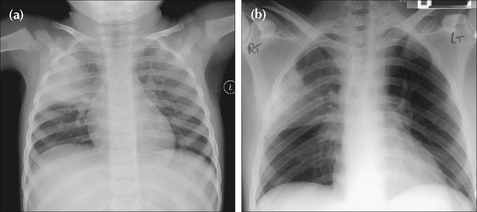

Figure 17.1 Precise clinical details are crucial for accurate analysis. Compare the CXRs of patients (a) and (b). (a) presents with a cough, fever and green sputum. An acute illness. The lung opacity represents a lobar pneumonia. (b) presents with weight loss and haemoptysis. The CXR shows similar lung shadowing to (a). However, given the clinical history, a simple lobar pneumonia is unlikely. The illness is not acute. The eventual diagnosis…bronchioloalveolar cell carcinoma of the lung.